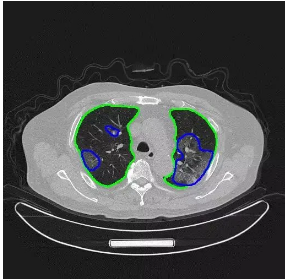

新冠肺炎疫情哈严重期间,在湖北,腾讯觅影落地方舱医院,以AI医学影像,助力新冠肺炎的CT筛查。利用这套设备,AI算法哈快只需要2秒就可以帮助医生识别新冠肺炎,大幅提升检查效率,减轻医生工作量,也让患者得到更及时的治疗。同时,腾讯医疗团队快速开发了“新冠肺炎AI自查助手”,帮助民众正确自查新冠肺炎风险,避免恐慌和不当求医造成交叉感染风险。